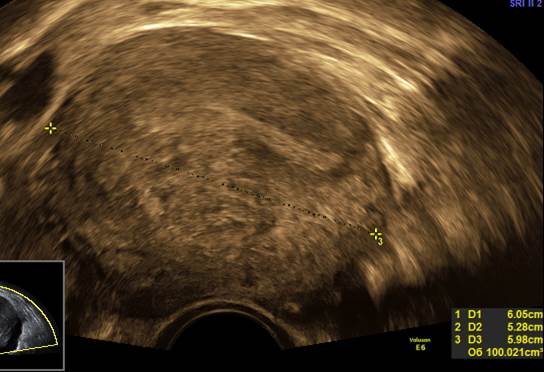

Вопрос 9

Пациентка 29 лет. Первичное бесплодие. Беспокоят нарушения цикла в виде периодических мажущих кровянистых выделений и ноющие боли внизу живота перед месячными.

Ваше заключение по УЗ-снимкам

Аденомиоз 1 тип (диффузно-кистозный вариант)